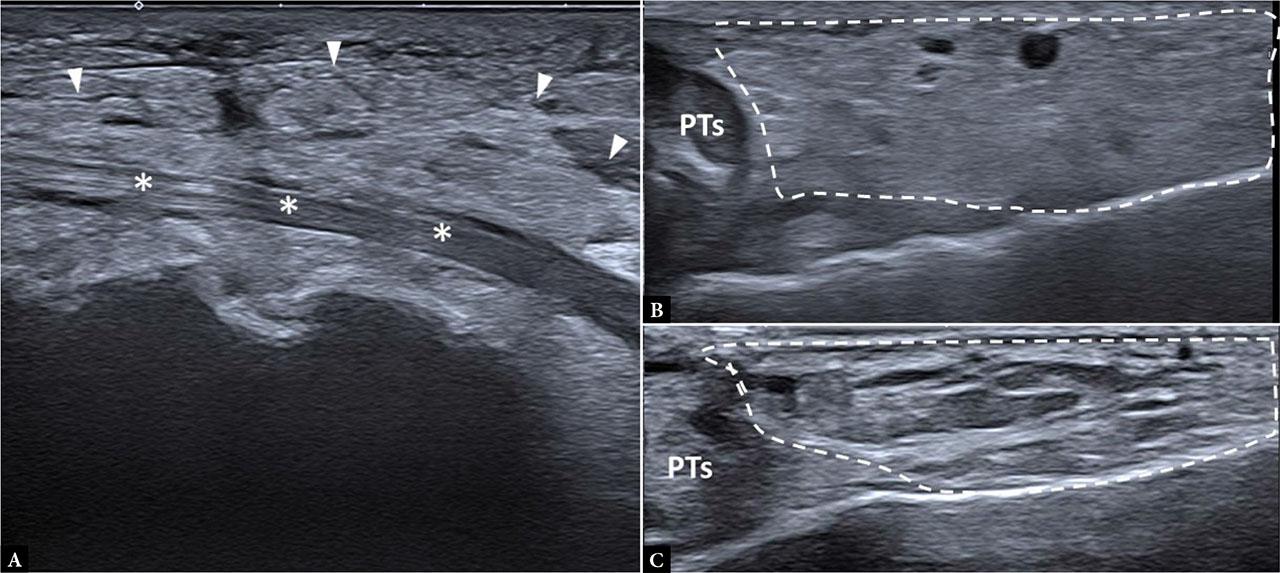

Overall, this tissue is susceptible to a wide spectrum of traumatic, degenerative, inflammatory, and neoplastic changes. However, it has limited patterns of response to injury; in most cases, the ultrasound appearance is non-specific and characterized by increased echogenicity, thickness, and vascularity, with a foggy appearance (Fig. 8).

Acute gout. A. Severe hyperechogenicity and loss of septal architecture in the adipose tissue surrounding the flexor digitorum longus tendon (*) in a 45-year-old man with acute pain and erythematous plaque at the medial aspect of the ankle. Spondyloarthropathy B. 37-year-old man with posterior ankle pain; B-mode image showing increased echogenicity of the posterolateral aspect of the ankle (dotted line); C. Comparative image of the contralateral ankle